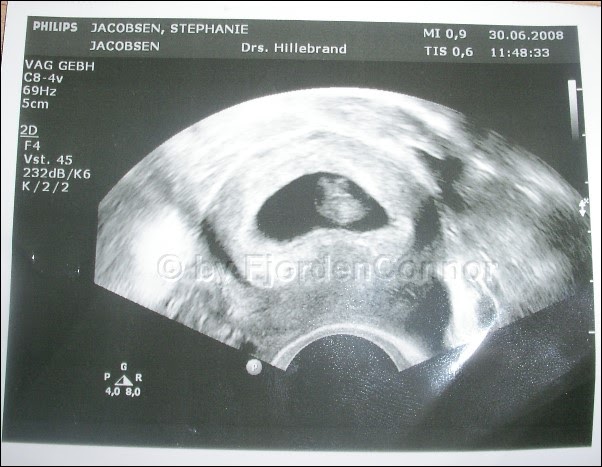

Ultraschallbild mädchen oder junge. Ich hätte zwar lieber ein mädchen gehabt aber dies kann man sich ja leider nicht aussuchen. März 2019 um 23 06. Was alles passiert ist und wieso ich ins krankenhaus musste. Geschlechterraten per ultraschall januar 2015 babyclub. Wann kann man per ultraschall das geschlecht erkennen. Seite 1 forum.

Ssw forum schwangerschaft urbia de. März 2019 um 12 56 letzte antwort. Meine frauenärztin konnte es beim termin daraufhin nicht bestätigen und meinte eindeutig ein mädchen da 3 striche zu sehen sind. Mein update zur 17. Mädchen outing 16 ssw. 18 ssw mädchen outing die große baby ultraschall bilderstrecke urbia de suche outingbilder 18. Mein liebstes doomoo stillkissen.